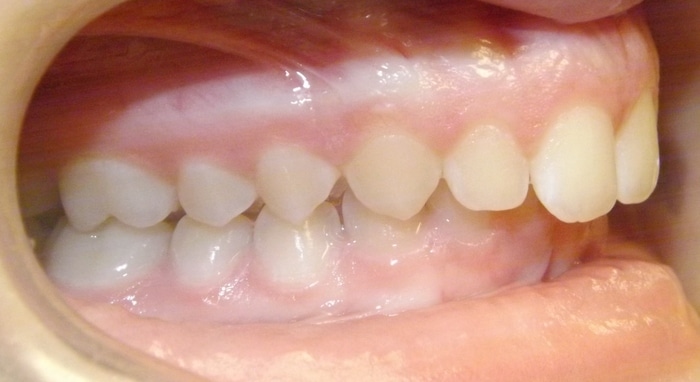

When Marlea presented to us she had a Class II bite with 100% overbite and a 5mm overjet. She also had upper spacing and lower crowding. Marlea’s treatment included metal braces with headgear. With her determination we were able to achieve a Class I bite as well as a perfect overbite and overjet! This is the perfect example of exemplary headgear wear and what a difference it makes in the final outcome of treatment.